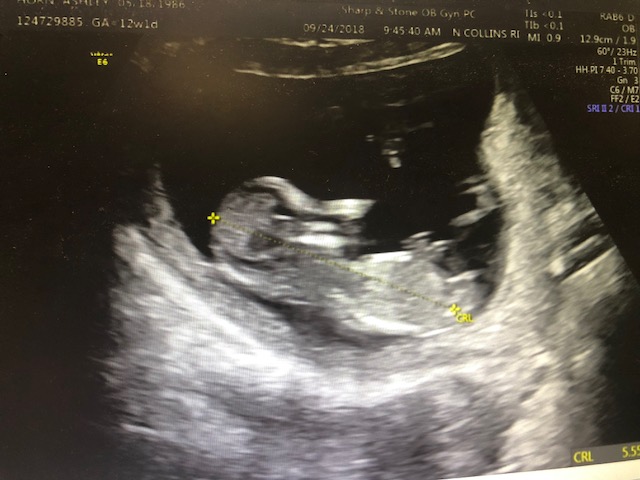

I didn't ask for a nub shot but is the nub visible in this pic? If so, do you think its a boy or a girl nub? Baby is 12 weeks and 1 day.

Tentative pink lean but it's very early and the nub could still rise. FX for pink!

Around 13 weeks is ideal for nub guesses. I'm leaning girl based on these pics.